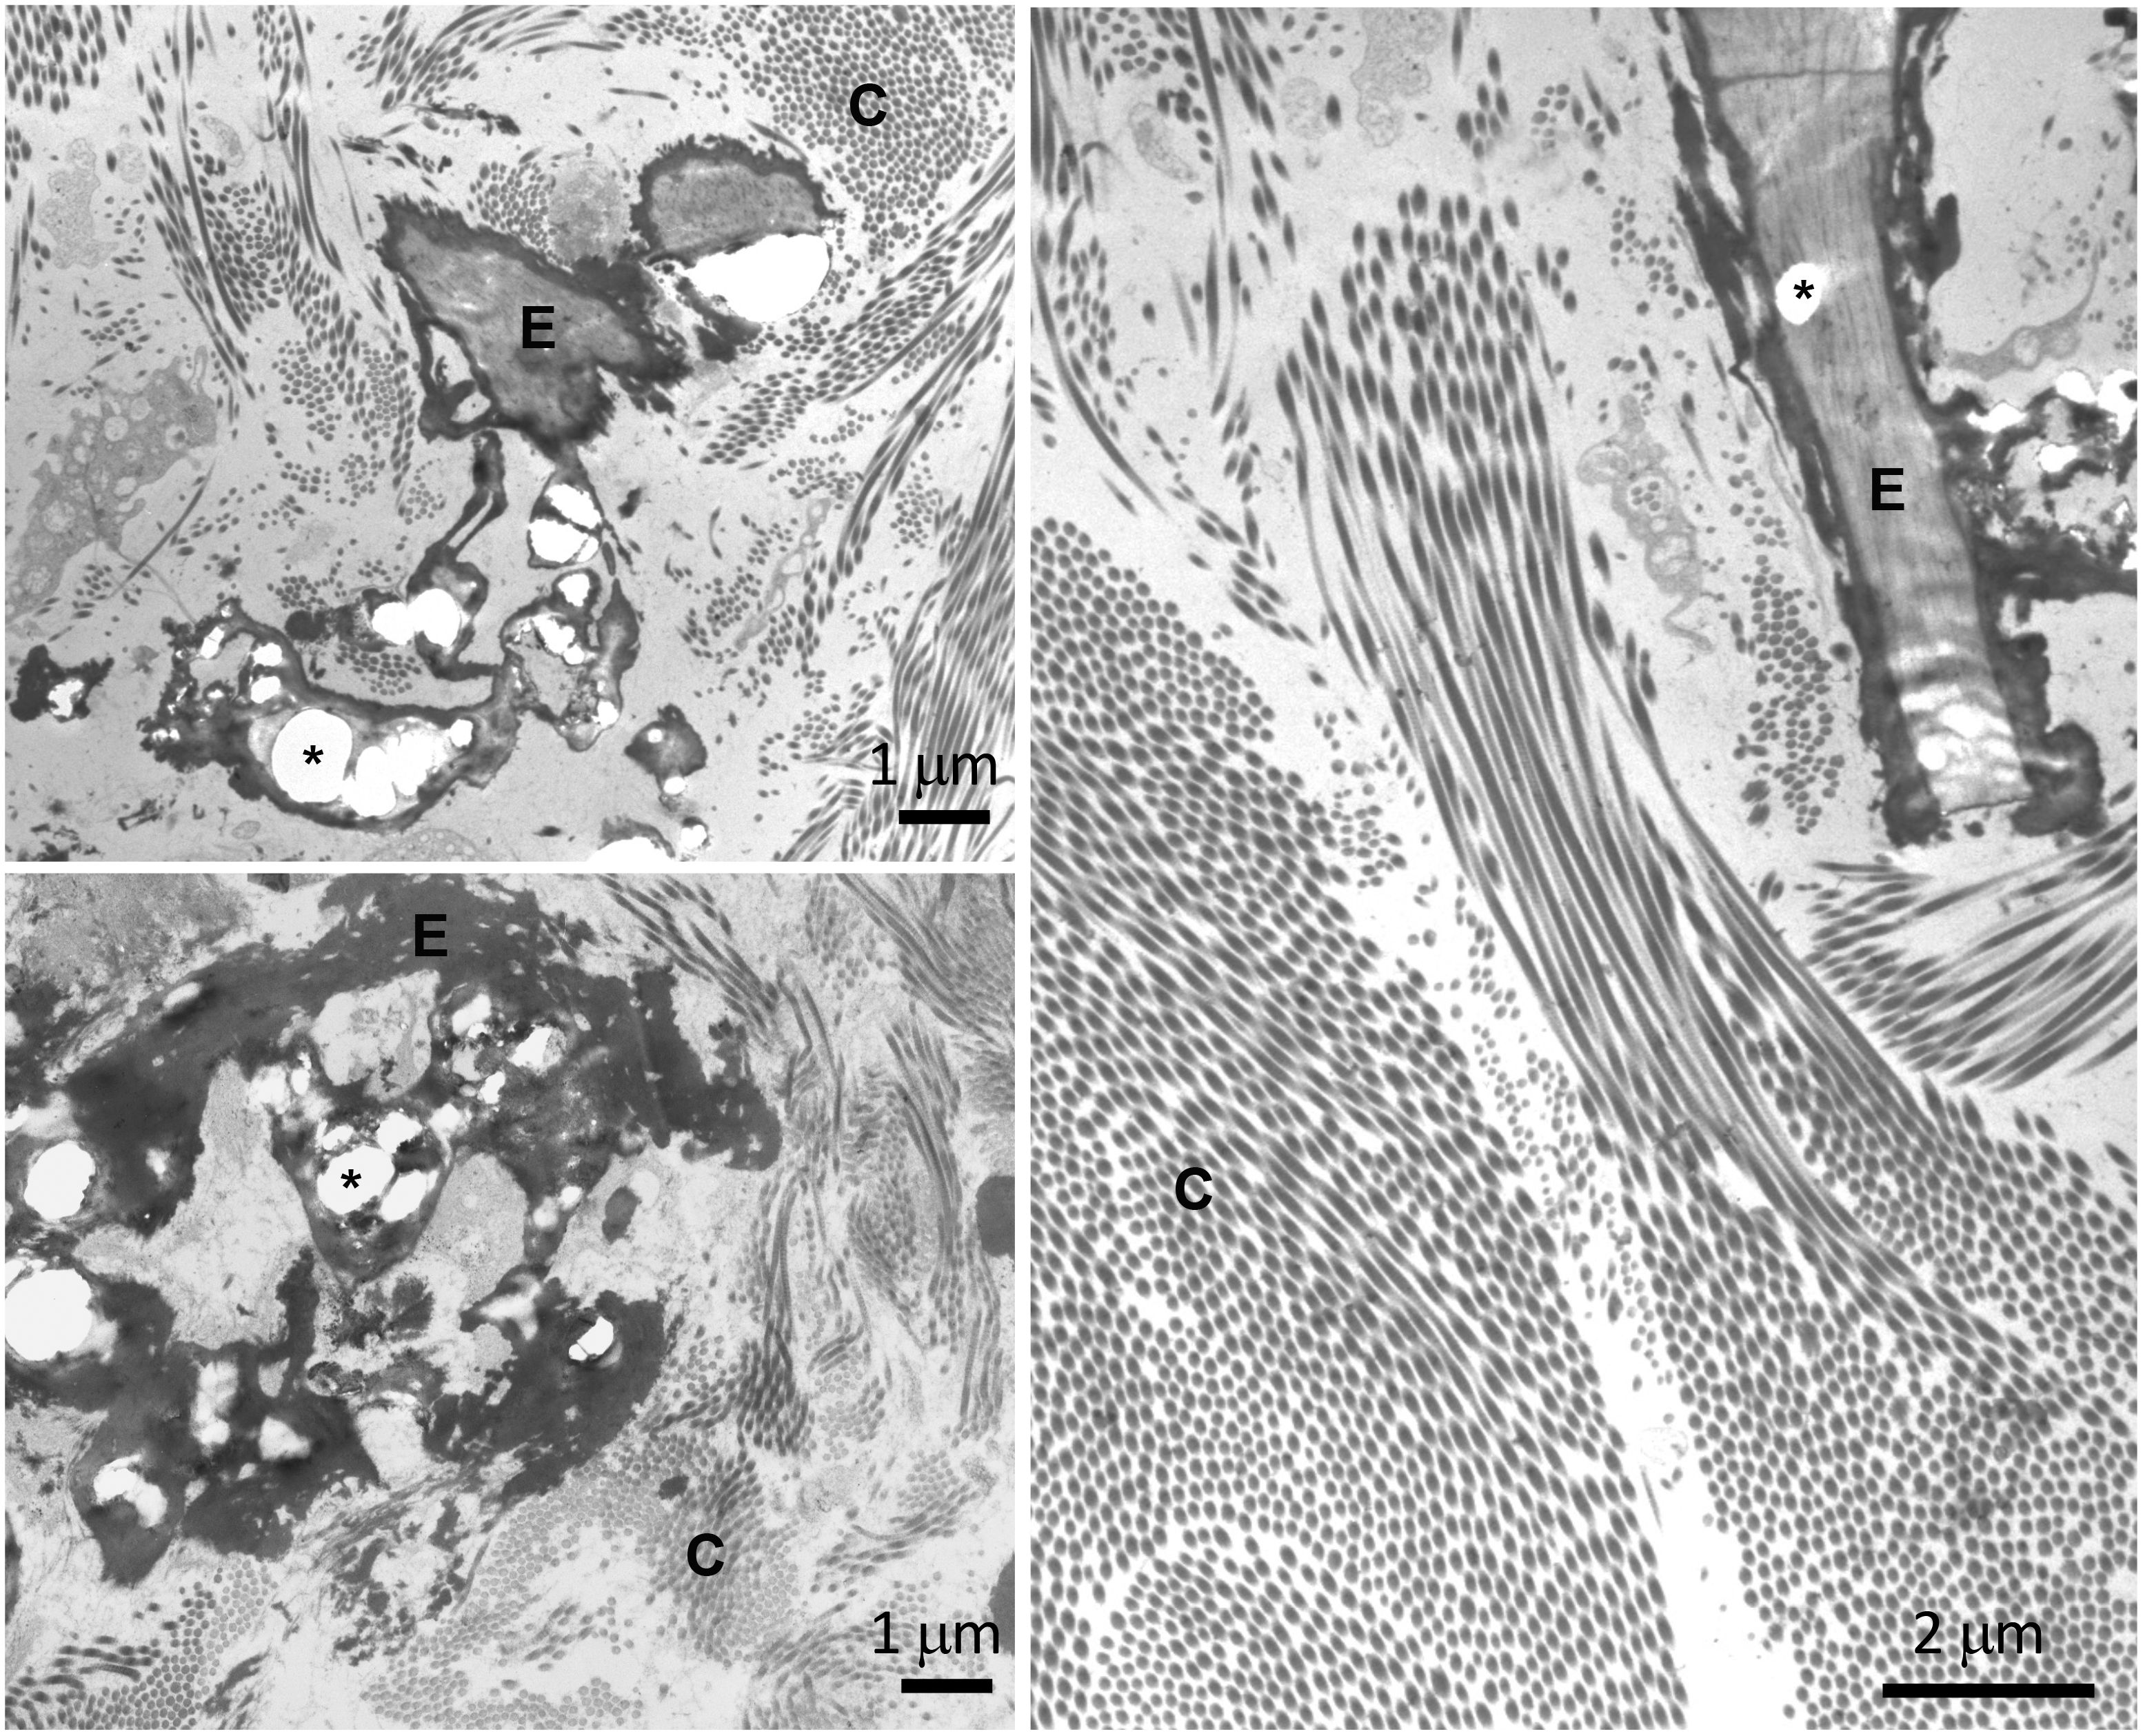

All patients received a clinical diagnosis of positive PXE for at least two major phenotypic diagnostic criteria (i.e., skin and ocular manifestations) (25). To further confirm the clinical diagnosis, biomolecular tests were performed on the ABCC6 gene. Homozygous or compound heterozygous for two rare ABCC6 sequence variants were found in 28 patients; in three patients, the second pathogenic variant was not detected; and in one patient, DNA for molecular testing was not available. Dermal biopsy was available for 10 patients: in all cases, ultrastructural analysis revealed collagen fibrils with heterogeneous diameters and the presence of fragmented and calcified elastic fibers in the reticular dermis (Figure 3).

Figure 3. Transmission electron microscopy of skin biopsies obtained from three pseudoxanthoma elasticum (PXE) patients (top left, bottom left ad right panels) showing collagen bundles (C) and elastic fibers (E). Calcified areas (asterisk) cause evident deformities of the amorphous structure of the fibers.